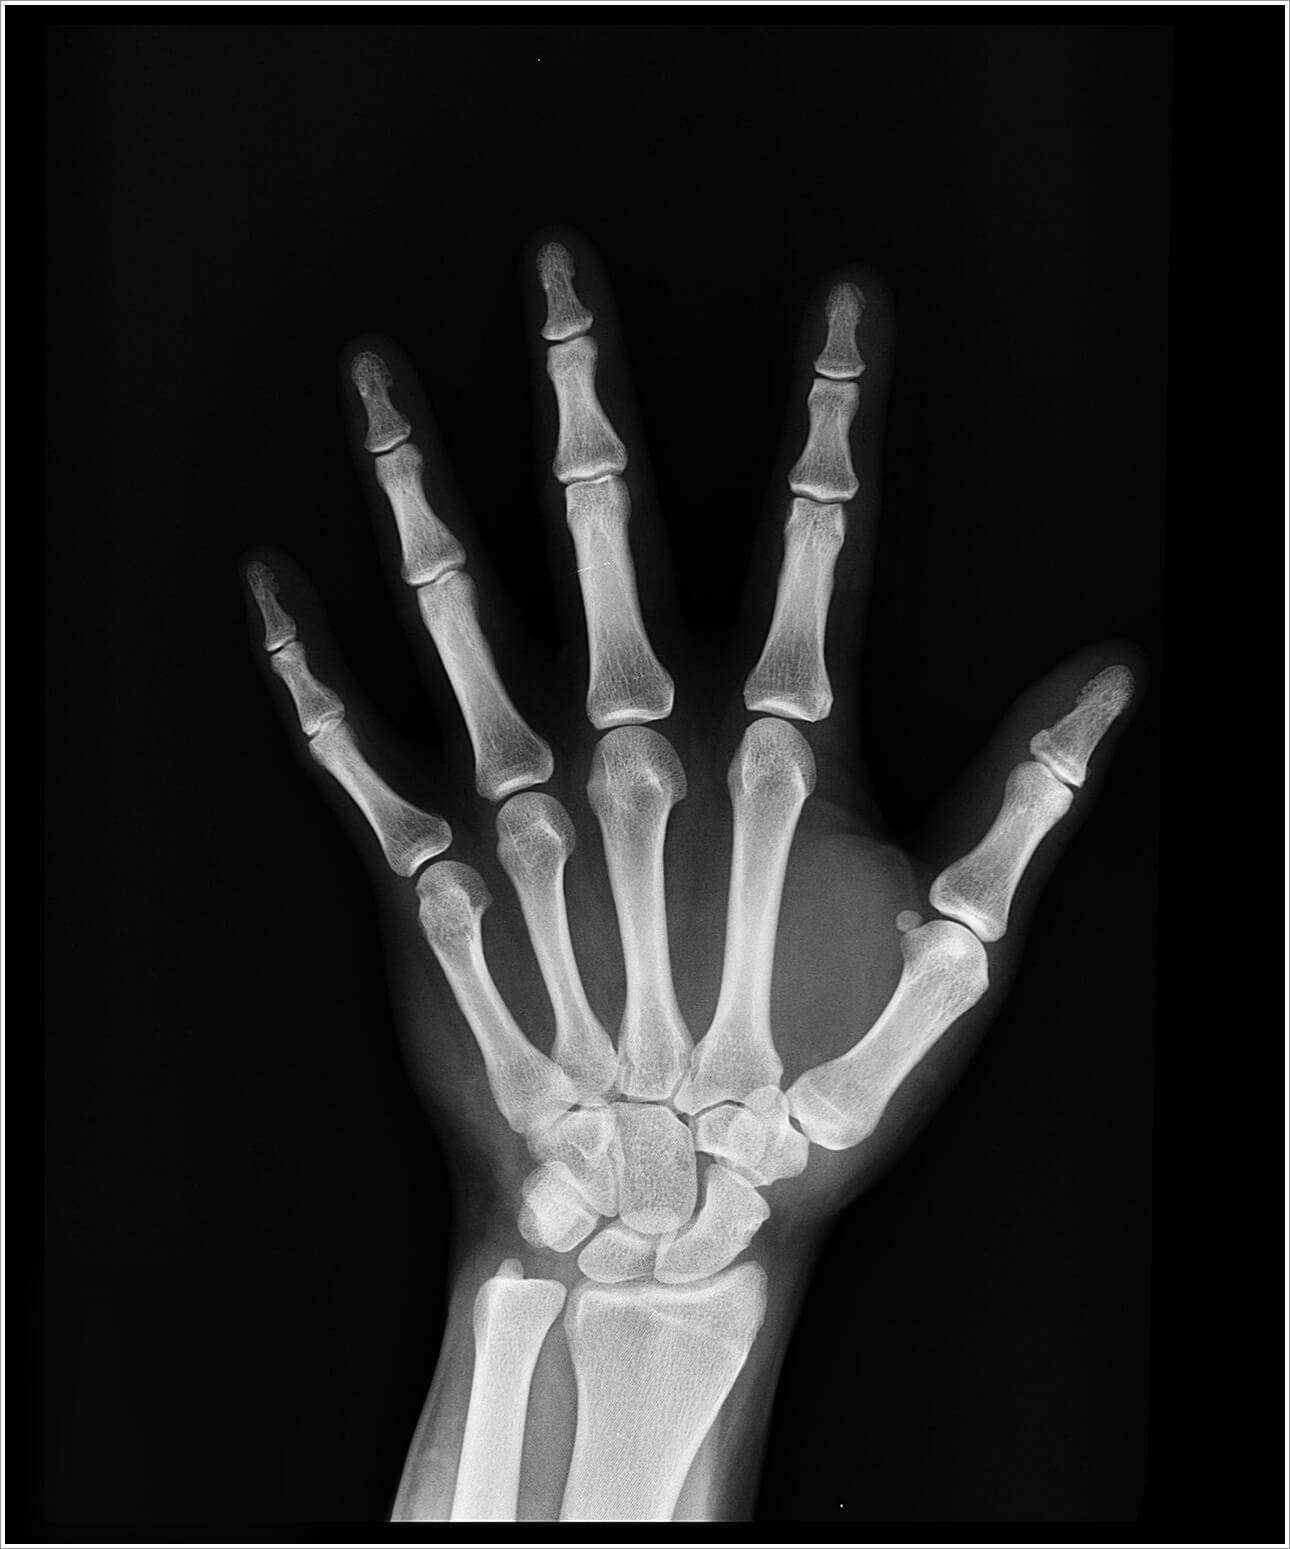

골절이 생기면 생각보다 완치까지 많은 시간이 걸린다. 특히 갈비뼈같은 곳이 골절되면 일상생활이 너무 불편해진다. 무릎 연골도 평소에 관리를 해줘야 하는데 그래서 더 빠르게 붙고 회복하기 위해 다양한 방법을 찾게 된다.

이는 나이가 더 들수록 회복까지 더 많은 시간이 걸리기 때문에 뼈골절에 좋은 음식을 먹으면서 생활 습관을 개선하는 것이 좋다. 합병증이 발생하기 전에 미리 뼈골절에 좋은 음식에 대해서 알아두도록 하자.